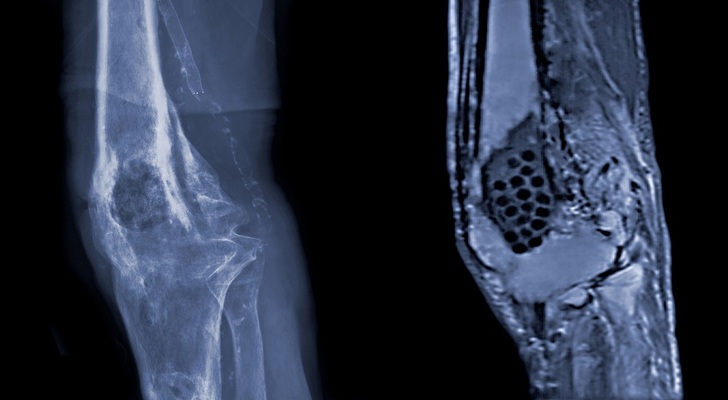

Osteomyelitis Symptoms, Causes and Diagnosis

Once it achieves the main target, bloodstream, the infection becomes rather dangerous and even life threatening. It may also expand from the tissue close to the bloodstream. The problem takes place inside the damaged bone. A disease processes the injured bone to microorganisms. Lower extremities and upper areas of top extremities are usually infected, especially when talking about little patients. As for the grown-up population, osteomyelitis will most likely occur in the spine (a.k.a. vertebrae).